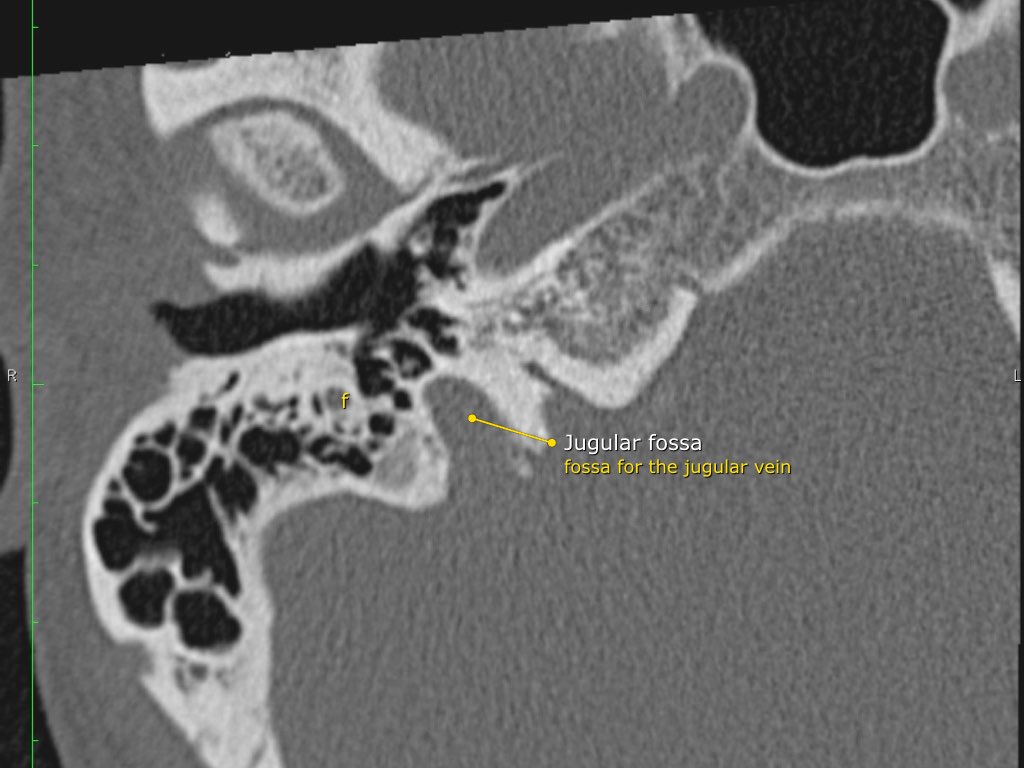

Trong bài tổng quan này, chúng tôi trình bày giải phẫu bình thường trên mặt phẳng cắt ngang (axial) và mặt phẳng cắt đứng ngang (coronal) của xương thái dương thông qua việc duyệt qua các hình ảnh.

Giải phẫu xương đá trên mặt phẳng cắt ngang (Axial)

Nhấp vào hình ảnh để phóng to.

Cuộn qua các hình ảnh.